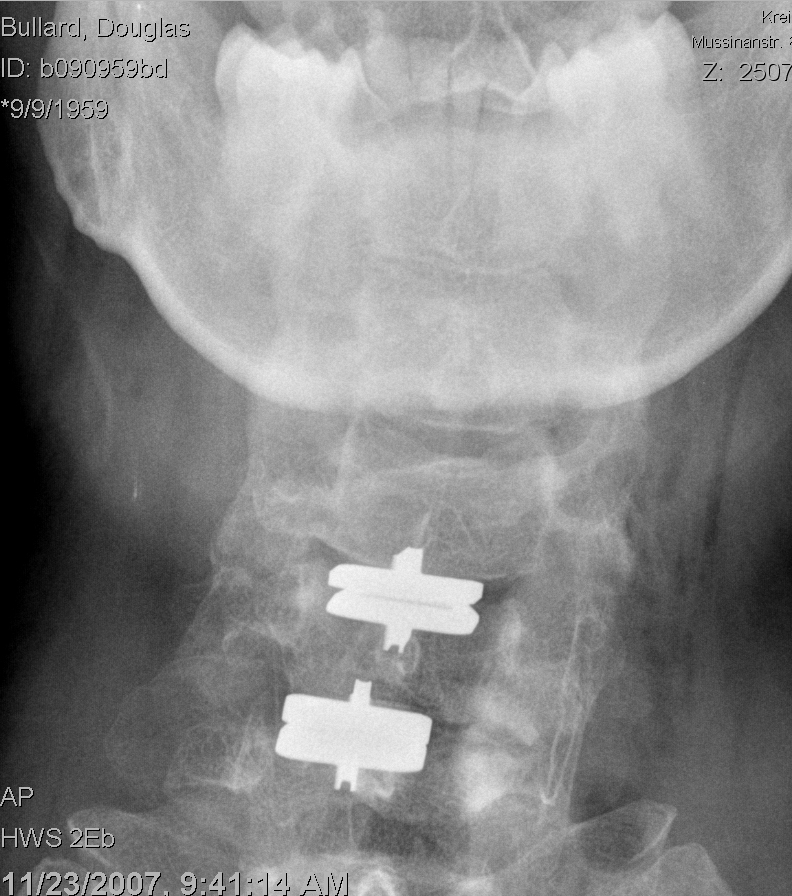

Post op front_sm

I was positioned exactly where the radiologist put me - I don’t normally lean to the left like this. Note the fin on the implant, which fits into the machined slot of the vertebrae.